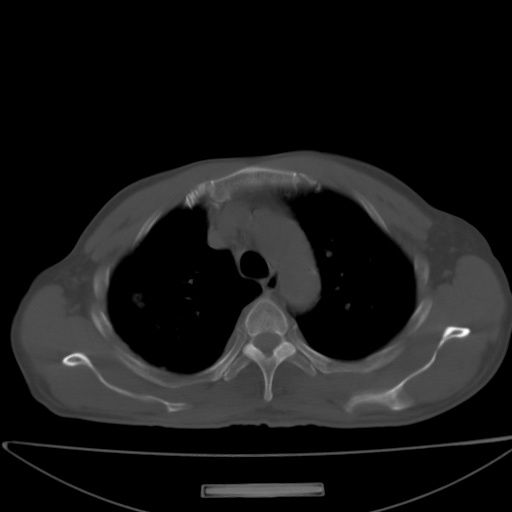

以下是引用jsgdoctor在2008-11-6 22:12:00的发言:[br]右主支气管壁明显增厚,管腔狭窄.考虑为右侧中央型肺癌伴阻塞性炎症\\肺脓肿.

以下是引用zjzjr在2008-11-6 20:25:00的发言:[br]中心型肺ca,合并阻塞性肺炎

以下是引用zsl6918在2008-11-6 19:43:00的发言:[br]右侧中心性肺癌(鳞癌)